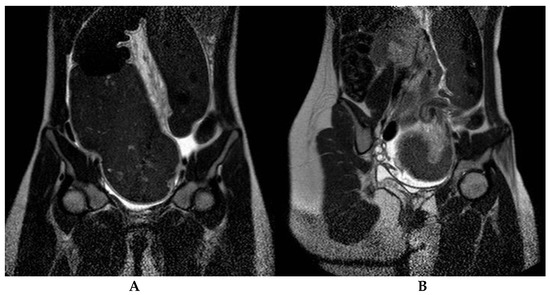

Colonic Volvulus in Children: Surgical Management of a Challenging Condition

by Francesca Destro, Luciano Maestri, Milena Meroni, Alessandro Campari, Federica Pederiva, Sara Costanzo, Giulia Del Re, Margherita Roveri, Gianvincenzo Zuccotti, Valeria Calcaterra and Gloria Pelizzo

Children 2021, 8(11), 982; https://doi.org/10.3390/children8110982 - 30 Oct 2021

Colonic volvulus (CV) is a rare but potentially life-threatening condition with unclear etiopathogenesis. To date, less than 80 pediatric cases have been described. Hirschsprung’s disease (HD) is associated with CV in 17% of cases, representing a significant risk factor. Non-HD CV is an [...] Read more.

Colonic volvulus (CV) is a rare but potentially life-threatening condition with unclear etiopathogenesis. To date, less than 80 pediatric cases have been described. Hirschsprung’s disease (HD) is associated with CV in 17% of cases, representing a significant risk factor. Non-HD CV is an even more complex entity. The aim of this study is to describe a series of patients with CV to accentuate some peculiar aspects of this disease. We performed a retrospective study (period: 2012–2021) collecting information of patients with CV. Data analyzed included: demographics, medical history, presenting symptoms and radiological and surgical details. Eleven patients (12.5 ± 2.8 years; 7F/4M) had CV (eight sigmoid, two transverse colon, one total colon). Five patients had associated anomalies and three had HD. A two-step approach with volvulus endoscopic/radiological detorsion followed by intestinal resection was attempted in eight cases (one endoscopic approach failed). Three patients required surgery at admission. At follow-up, two patients developed recurrent intestinal obstruction, one of whom also had anastomotic stenosis. Colonic volvulus is a challenging condition that requires prompt patient care. A missed diagnosis could lead to severe complications. The evaluation of the patient should include a careful histological examination (searching for HD and alpha-actin deficiency), immunologic and metabolic screening, neurological tests and detection of chronic intestinal pseudo-obstruction (CIPO). Lifelong follow-up is mandatory for the early recognition and treatment of progressive diseases involving the proximal gastrointestinal tract. Full article

Show Figures

Figure 1